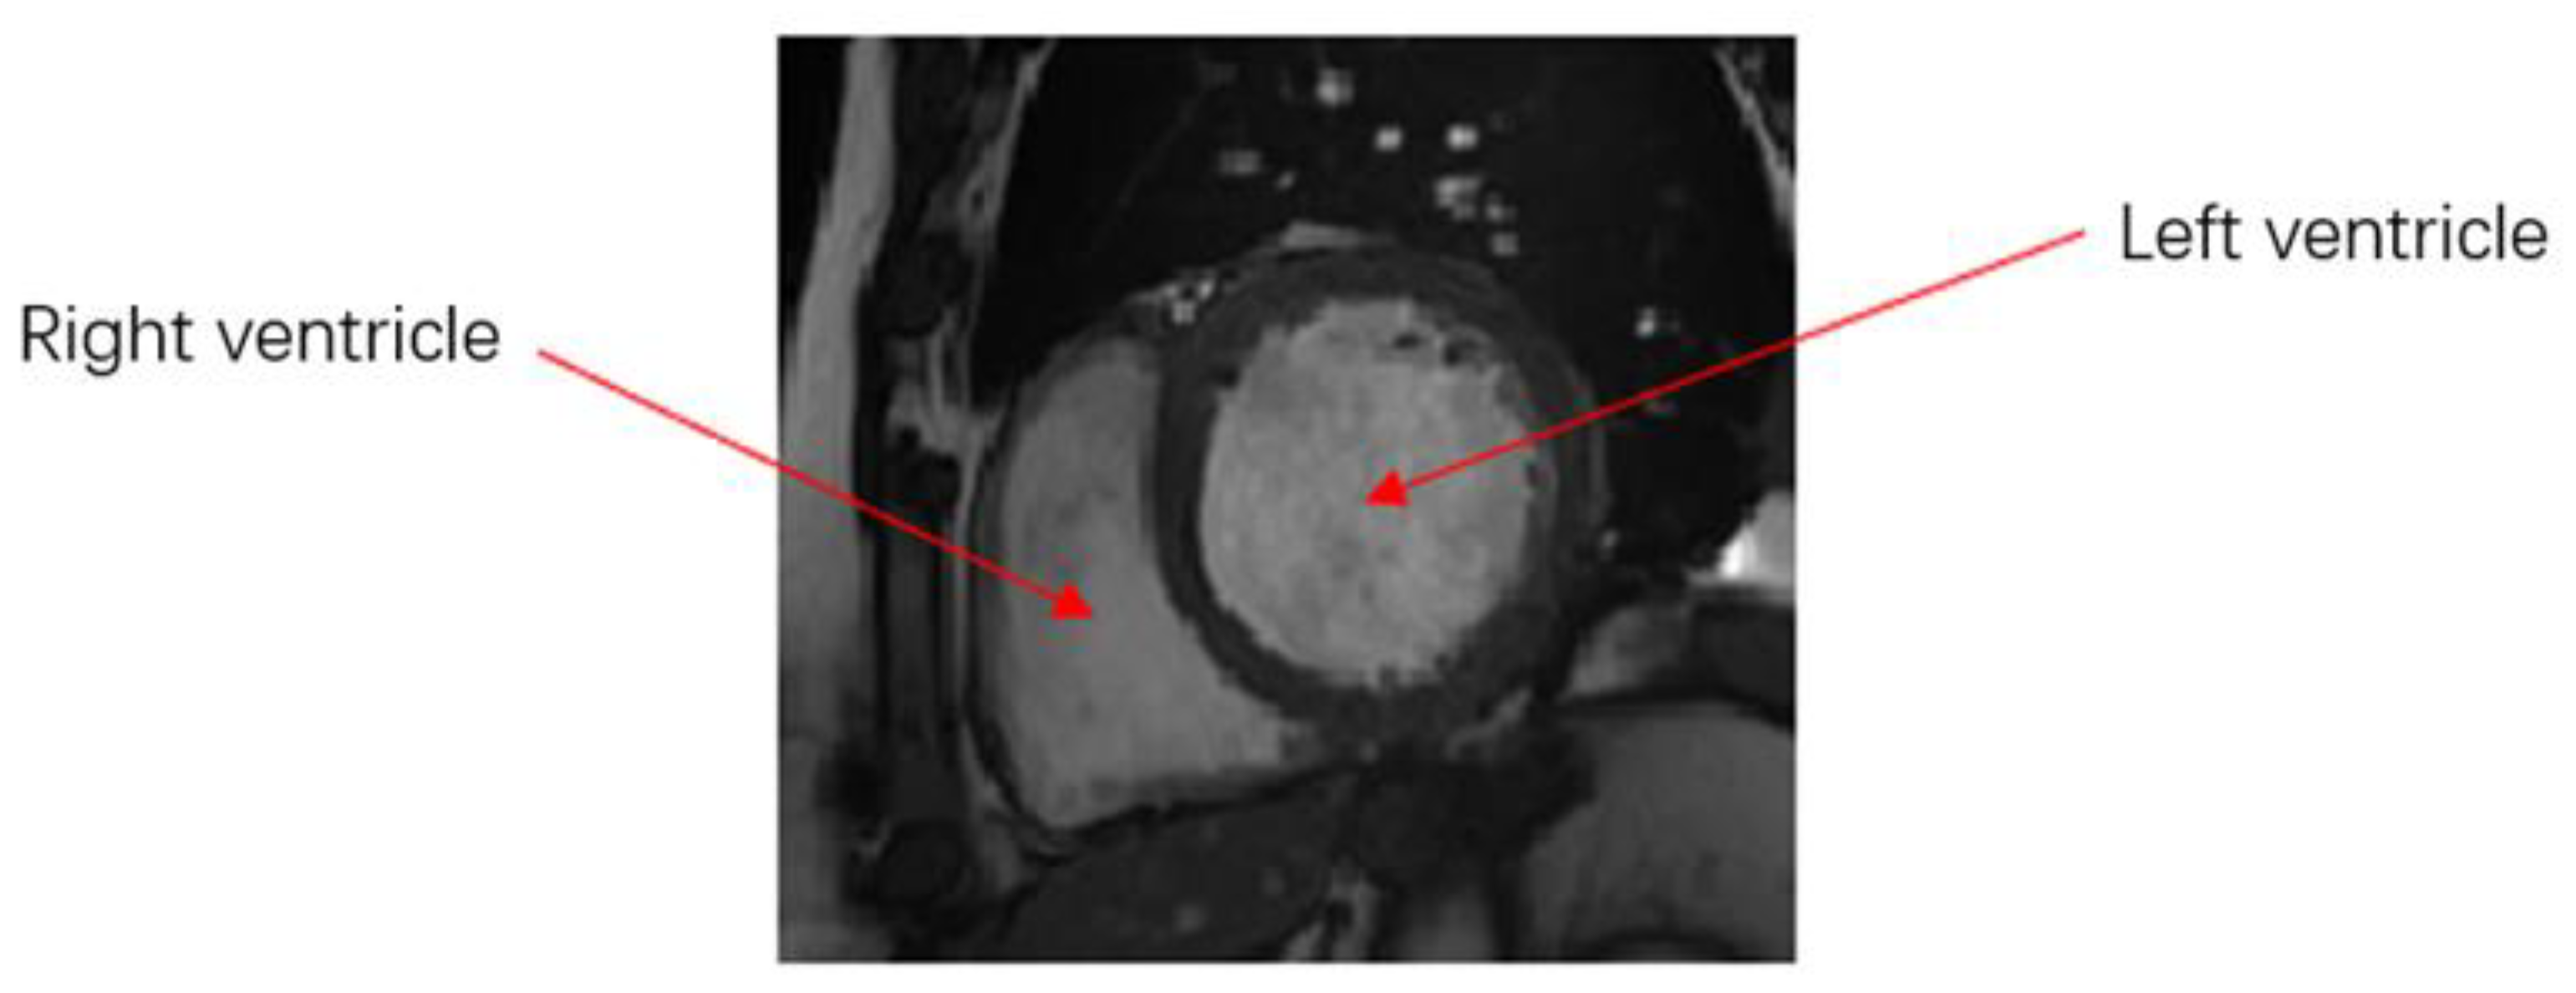

The results of right ventricle segmentation by the U-Net network are shown in Figure 5, which shows three groups of images, each of which is divided into three pieces. Figure 5a,d,g shows the input feature image, Figure 5b,e,h, which are the resulting images of the U-Net network segmentation, and Figure 5c,f,i is the gold-standard image marked by experts.

It may be observed from Figure 5b,c that the result of network segmentation was consistent with the result image marked by experts. However, it may be observed from Figure 5e,f that the network-segmented and expert-labeled images were under-segmented at the apex of the heart. It may be observed from Figure 5h,i that the network-segmented image and expert-labeled image exhibit the problem of over-segmentation near the ventricular wall. The position shown in the red circle represents the difference between the gold-standard image and the segmentation prediction area. Therefore, although the results of the U-Net network were feasible for segmentation of the right ventricle, there was an error in the segmentation of images with complex ventricular shapes.

Figure 5. Comparison of network segmentation results. (a) The input feature image. (b) The resulting images of the U-Net network segmentation. (c) The gold-standard image marked by experts. (d) The input feature image. (e) The resulting images of the U-Net network segmentation. (f) The gold-standard image marked by experts. (g) The input feature image. (h) The resulting images of the U-Net network segmentation. (i) The gold-standard image marked by experts.